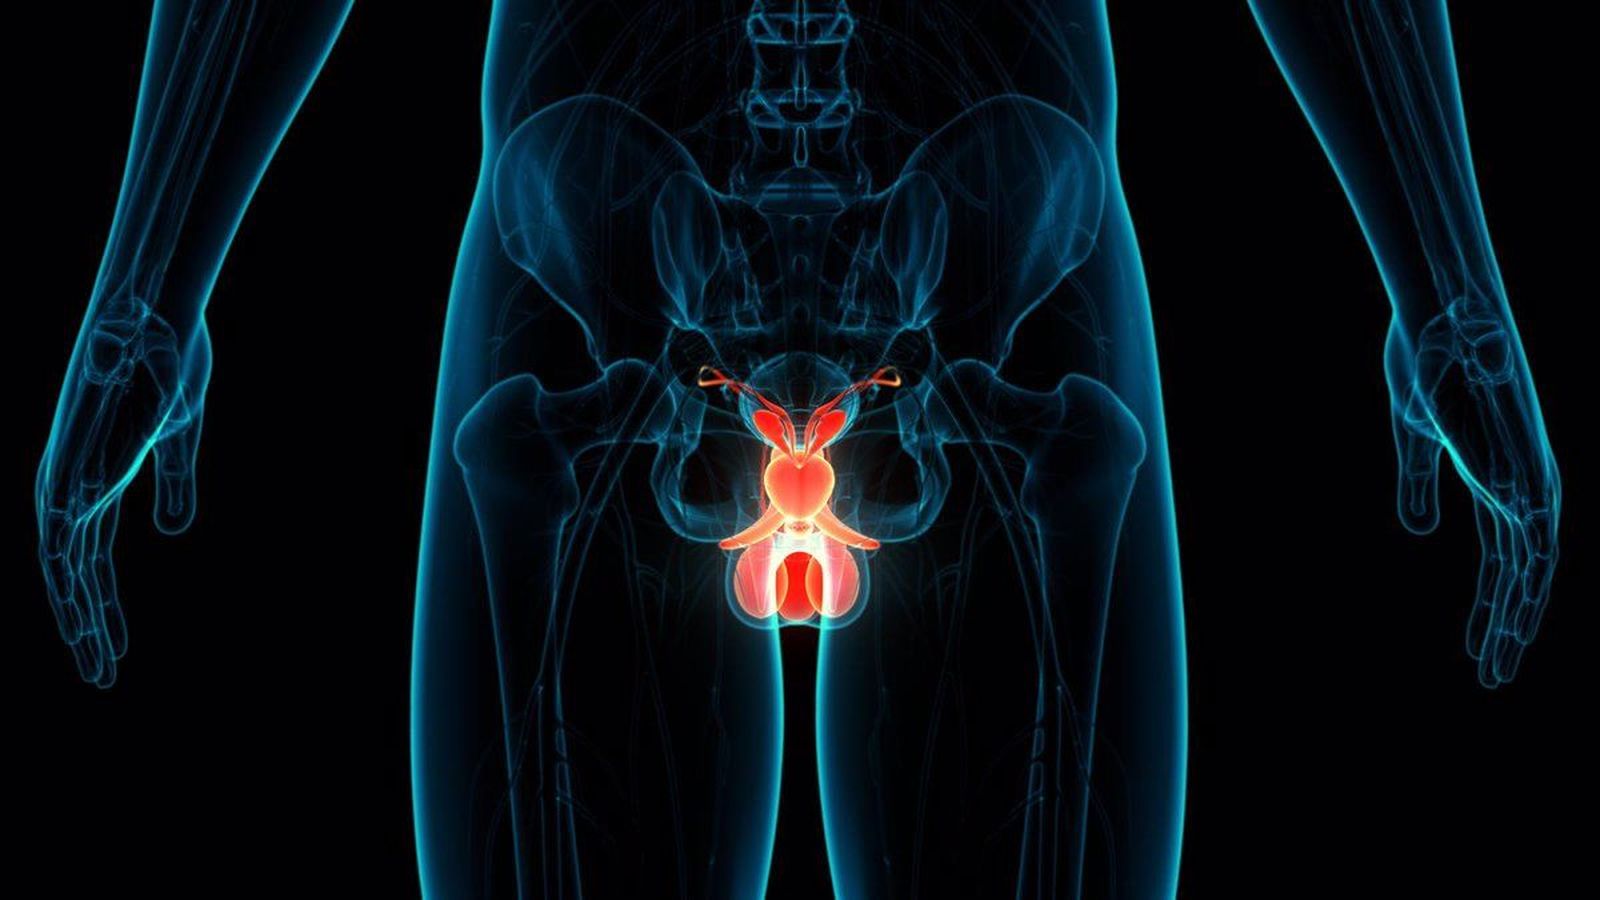

El urólogo ha explicado que la próstata es un órgano situado justo debajo de la vejiga y la uretra la atraviesa, por lo tanto, "los síntomas siempre estarán relacionados directamente con ella". Entre los principales, o los más conocidos, fundamentalmente a medida que los hombres envejecen, destacan un retraso en el inicio de la micción, es decir, dificultad para empezar a orinar, así como un chorro urinario mucho más débil.

Actualmente, existen herramientas novedosas para tratar la próstata. Es el caso de las técnicas de imagen, como la resonancia multiparamétrica de la próstata. "No sólo permite hacer un análisis mucho más preciso de la probabilidad de que haya una lesión en la próstata, sino también realizar una biopsia muchísimo más precisa que la que hacíamos hace años", ha resaltado el especialista.

Mientras que, antiguamente, la biopsia de próstata se hacía de forma aleatoria, es decir, "cogías varios puntos de la próstata y los mandabas a analizar", ahora, la llamada biopsia de fusión "permite ir a los puntos más sospechosos donde está esa lesión que te ha dado la resonancia. Eso ha permitido diagnosticar muchísimos más cánceres".